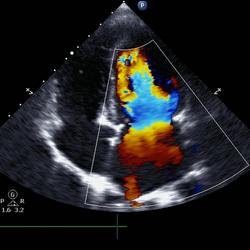

Ecocardiograma

É um dos exames mais importantes quando falamos em cuidados relacionados ao coração. Avalia a estrutura e função cardíaca e detecta doenças valvares.